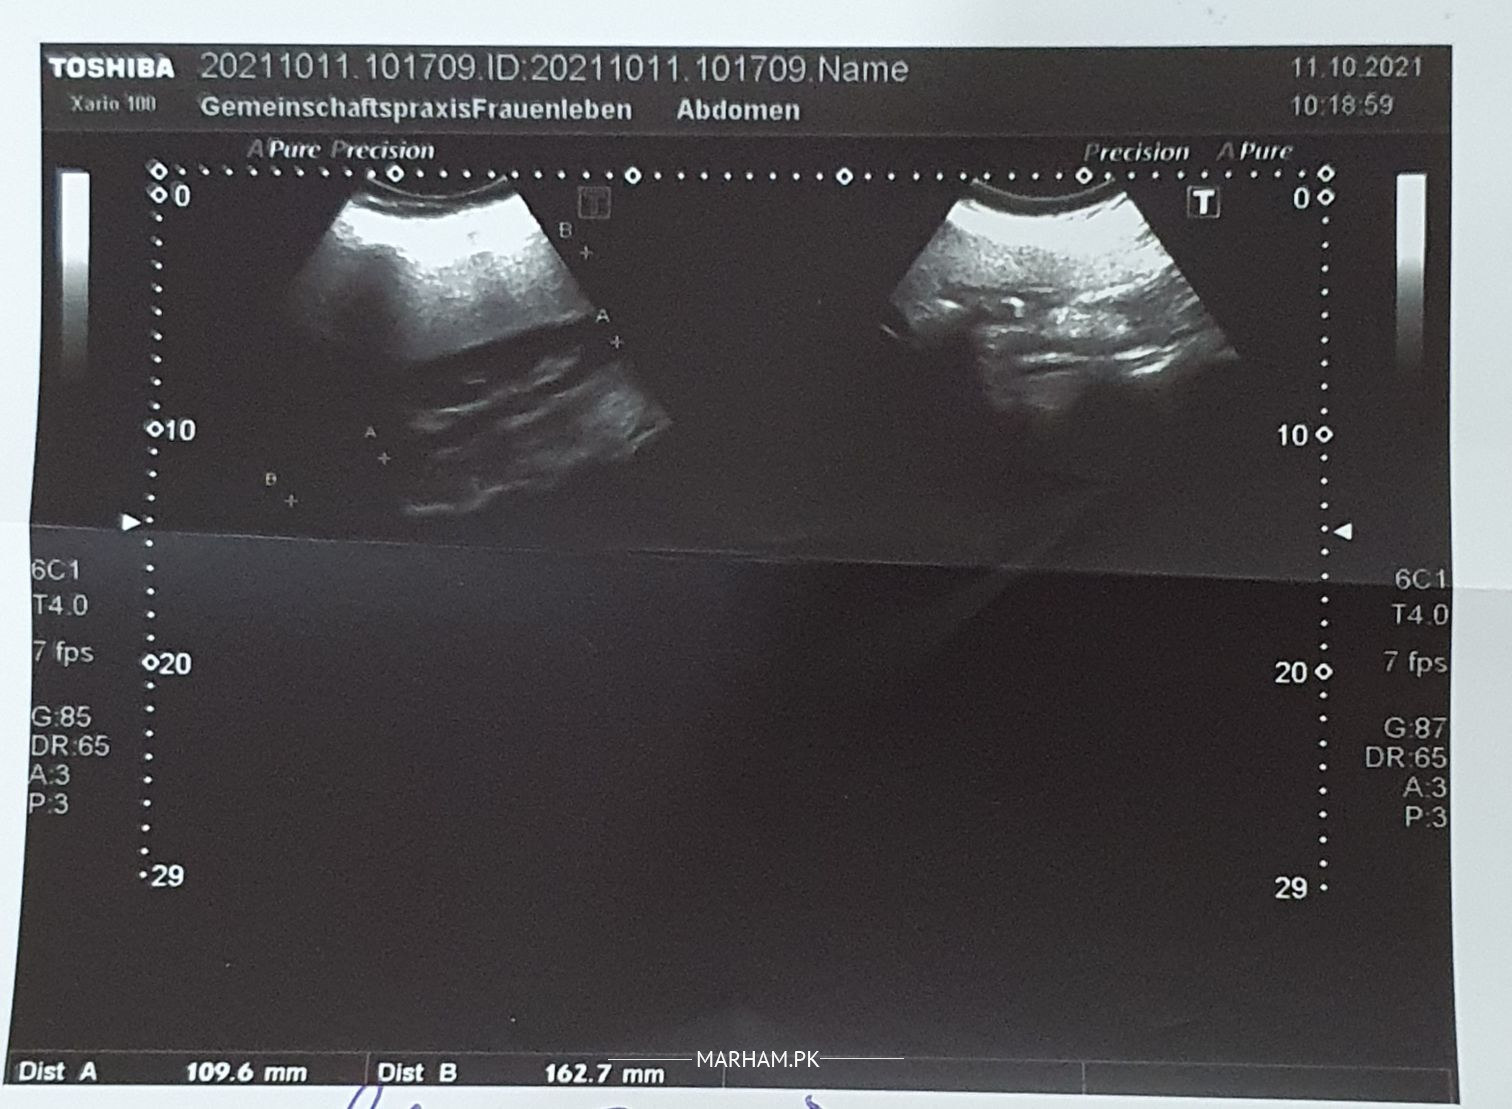

asalam o alikum deer doctors. Meri walida ka pitty ma patheri uska operation krwa kerwa tha to doctor ny urlta sound ka bola tha wo krwaya to pata chala ke masany ma bhe pathri hai

Ya reports ki photos hai. Kiya unka kidneys ma bhe pathri hai ? Or is pathri ka liye kiya elaj sahi rhy ga

stone at the junction of left ureter and bladder.. 1.4cm according to report.. may move itself or may need removal